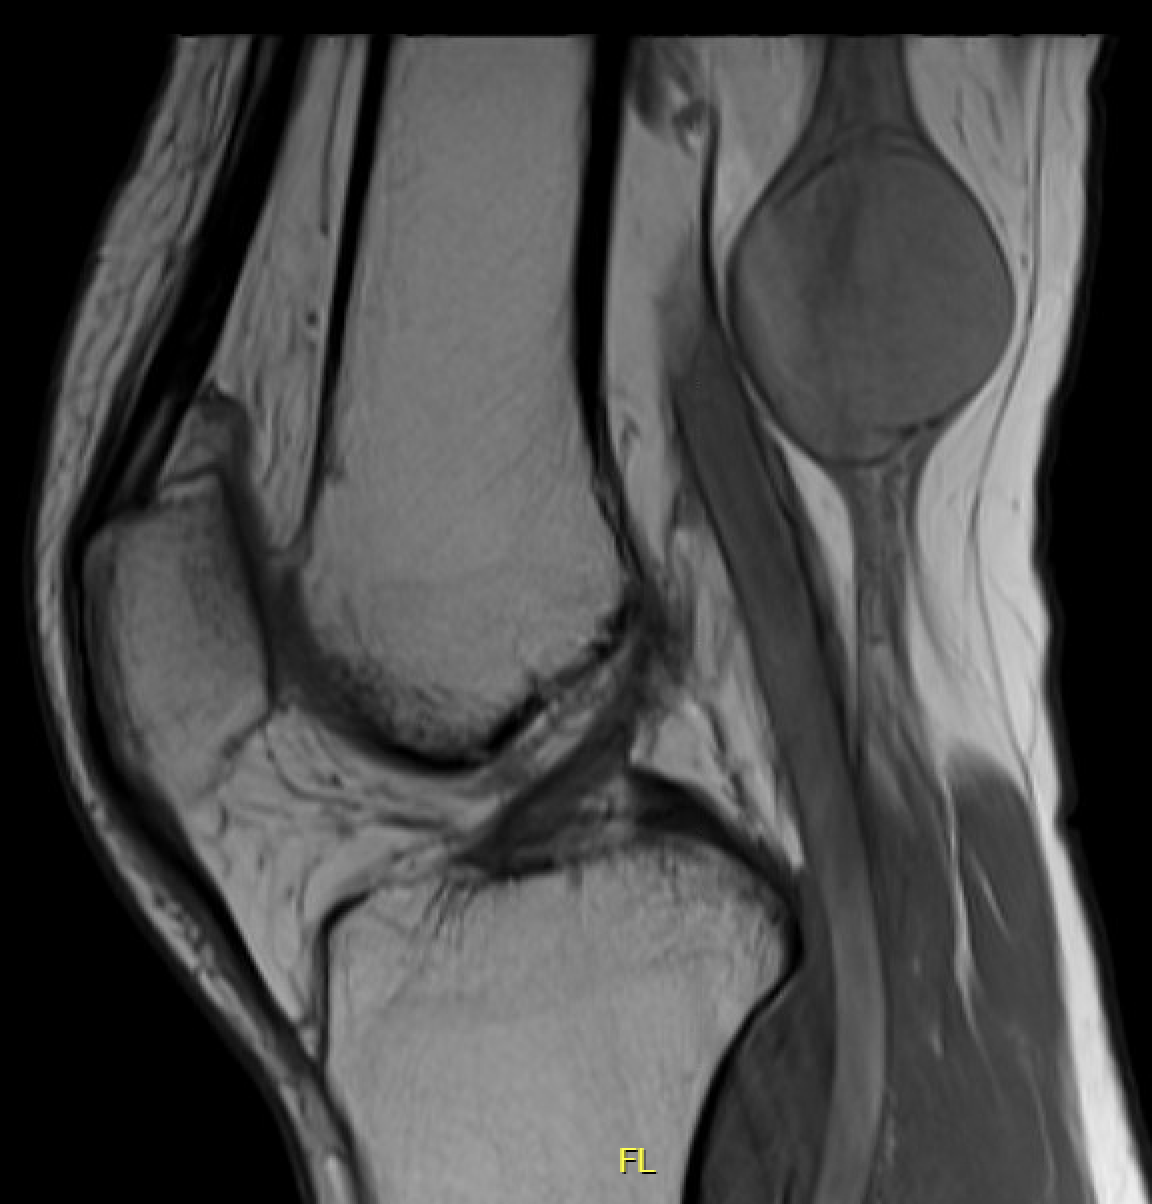

MRI

Target sign

- hypointense centrally

- hyperintense peripherally

Neurofibroma common peroneal nerve